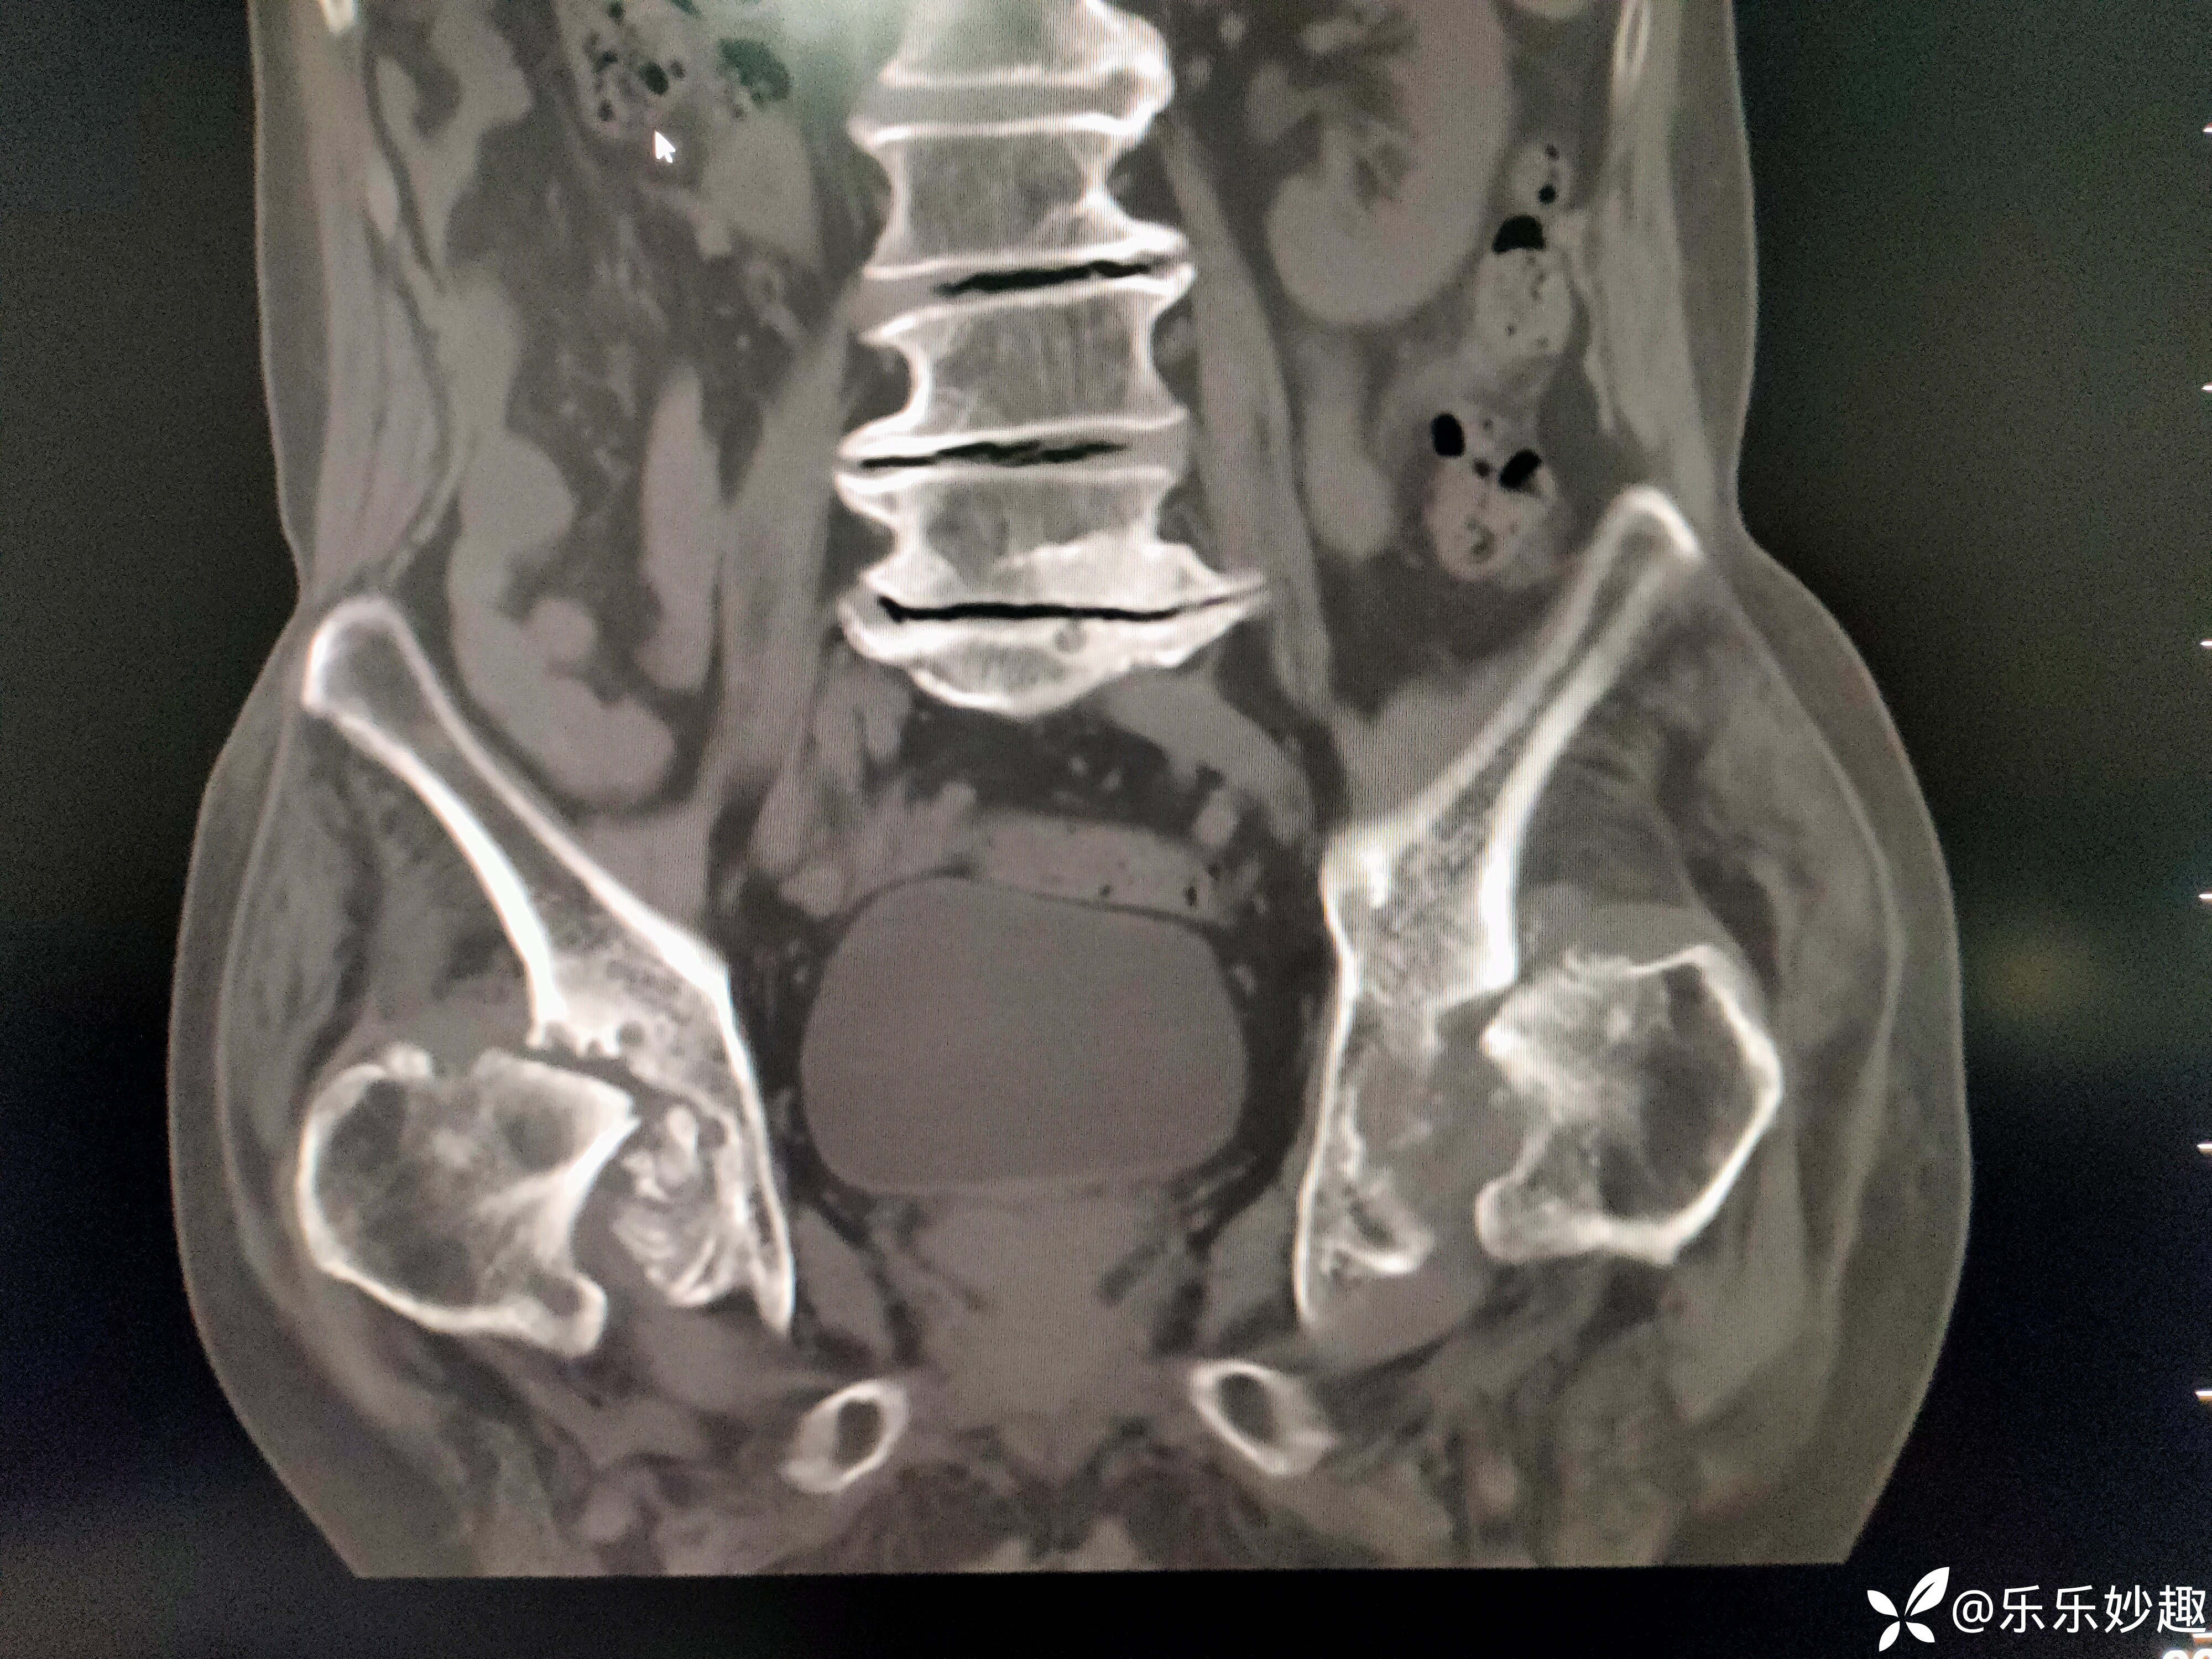

然后做了CT,见下图